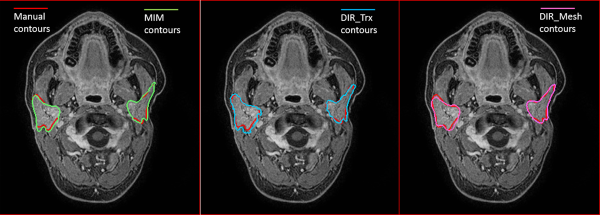

Qualitative results of contour propagation using MIM, DIR_Trx, and DIR_Mesh are presented in Figure 2, showing a good agreement between the manual reference contours and the propagated ones, without evident differences among the 3 methods. Quantitative results of contours evaluation are reported in Table 3. Average symmetric distance, MSD, and DSC indices calculated on both PGs for all patients and for all 3 considered DIR methods are plotted in Figure 3. DIR_Mesh presented the lowest average values of ASD and MSD and the highest average value of DSC over the population among the 3 methods, although nonsignificant (P values of the nonparametric Kruskal-Wallis test = 0.57, 0.40, and 0.27 for ASD, MSD, and DSC, respectively). The average propagation errors with respect to the reference contours are lower than the voxel diagonal (2 mm), and DSC is around 0.8, generally considered as the threshold for good agreement.

Figure 2

Examples of contour propagation using MIM (left), DIR_Trx (center), and DIR_Mesh (right) methods. Manual reference contours are also reported in red.